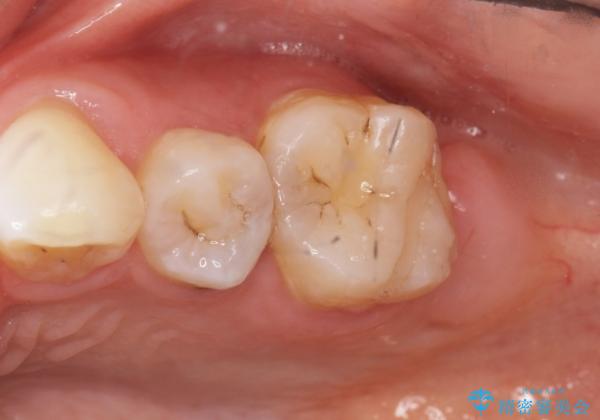

- 歯と歯の間の虫歯治療を希望された患者様です。

フロスを通すと臭いのが気になるとの事でした。

精査したところ、左上の奥歯の間(左上56間)にう蝕を認めました。

う蝕を丁寧に除去したのち、セラミックインレーによる修復を行いました。